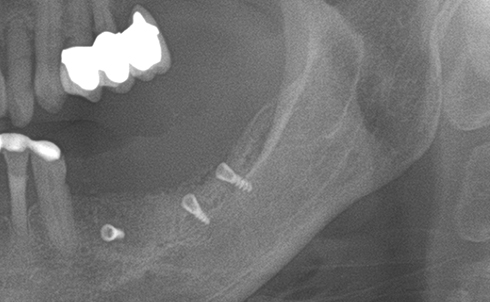

Implants/Bone Grafting

Partial edentulous clinical cases